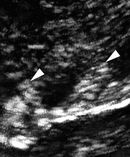

يتم تنفيذ كلا من تصوير الإثنى عشر وتصوير القولون كفحص البطن باستخدام وضع معيار بى وتدفق اللون وفحص الأعضاء بالموجات فوق الصوتية وفقا لنظرية دوبلرباستخدام محول تردد منخفض على سبيل المثال 2.5 ميغاهيرتز ومحول تردد عال على سبيل المثال 7.5 ميغاهرتزمسبار. وتجرى دراسة تفصيلية للجدران العفجية والطيات، وجدران القولون والجزء المنبعج من جدار القولون باستخدام 7.5 ميغاهرتز مسبار. وتفحص هياكل عميقة في البطن باستخدام 2.5 ميغاهرتز مسبار. وتجرى جميع الاختبارات فوق الصوتية بعد صيام ليلة وضحاها (ما لا يقل عن 16 ساعة) باستخدام معيار الفحص الداخلي. وتفحص المواضيع مع وبدون أشعة الماء. وتجرى تصوير أشعة الماء في وجود أدوات بالغة تأخذ ما لا يقل عن لتر واحد من الماء قبل الفحص. ويتم فحص المرضى في وضع الاستلقاء، وضع خلفي منحرف، وفى وضع الاستلقاء على الجانب الأيسر باستخدام معياربين الضلوع وتحت الضلوع. وغالبا ما يتم تقييم الكبد والمرارة والطحال والبنكرياس والإثنا عشر والقولون والكلى في جميع المرضى. مع المريض المستلق على ظهره، فحص الإثنى عشر بالموجات فوق الصوتية عالية التردد يتم مع 7.5 ميغاهرتز مسبار وضع في الجزء العلوي من البطن، ووسط الشرسوفي على التوالي ؛ لتصوير القولون بالموجات فوق الصوتية عالية التردد، القولون الصاعد، يفحص من نقطة البداية عادة في منتصف الطريق على خط وهمي يمتد من عرف الحرقفة إلى السرة والشروع في رأس الأمشاط cephalid عن طريق يسار منتصف البطن؛ بالنسبة للقولون النازل، يبدأ الفحص من الجزء العلوي من البطن وتستمر نحو الذنب caudally ويجتاز منتصف يسارالبطن وأسفل يسار البطن، لينتهي في القولون السيني في منطقة الحوض السفلي. ويستخدم تخطيط دوبلر التصواتى بتدفق اللون فوق الصوتي لدراسة تمركز الآفات بالنسبة للأوعية. ويتم تنفيذ جميع القياسات من قطر وسماكة الجدار ببرمجيات الدمج. ويتم أخذ القياسات بين موجات تمعجية.

أرباع البطن الممسوحة في ترتيب. جدار الإثنى عشر ثلاثي الموجات مع طيات كيركرينج، والتي تبين المعومين بالمياه المتباينة. منظر عال الدقة لانتفاخات القولون.